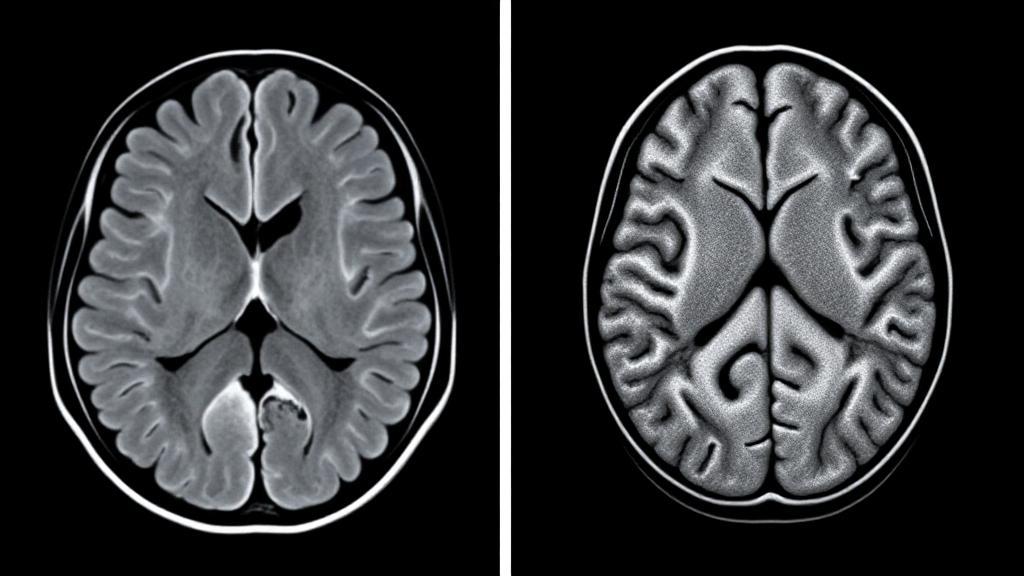

When it comes to brain imaging, two of the most commonly used techniques are CT scans and MRI scans. Both have their unique advantages and limitations, making them suitable for different scenarios. Understanding the differences between these imaging modalities is crucial for determining which is better suited for specific medical needs.

CT scanning uses X-ray technology to create detailed cross-sectional images of the brain. Multiple X-ray beams and electronic detectors rotate around the patient, capturing data that computers transform into detailed images.

MRI technology employs powerful magnets and radio waves to generate detailed images of brain tissue. Unlike CT scans, MRI does not use ionizing radiation.

Image Quality and Detail

CT Scan Strengths

- Excellent for detecting:

- Acute bleeding

- Skull fractures

- Calcifications

- Large tumors

MRI Strengths

- Superior for visualizing:

- Soft tissue details

- White and gray matter

- Small tumors

- Multiple sclerosis lesions

- Blood vessel abnormalities